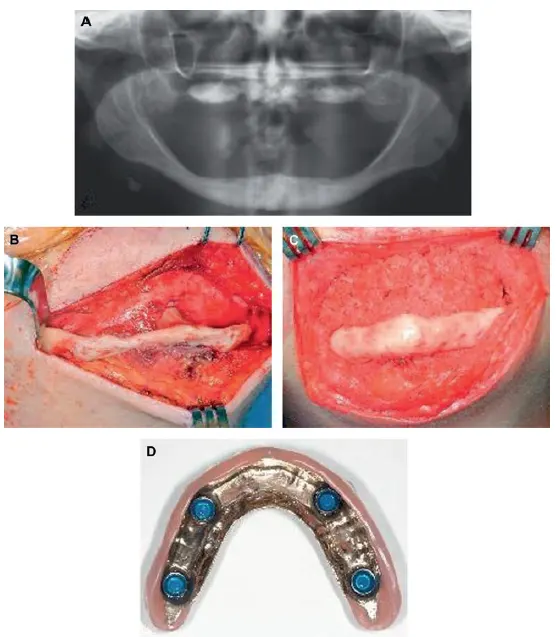

شکل VIII‑6. افزایش حجم فک پایین بیدندانِ تحلیلرفته

A: تصویر رادیوگرافی قبل از عمل جراحی.

B: نمایان کردن فک پایین تحلیلرفته از طریق رویکرد جراحی خارجدهانی (Extraoral Approach).

C: قرار گرفتن گرافت استخوانی در محل؛ این گرافت ترکیبی از پروتئینهای القاکنندهٔ استخوان (BMP)، سلولهای بنیادی استخراجشده از مغز استخوان تیغهٔ خاصره (استخوان ایلیاک) و استخوان خشکشده منجمد بود.

D: تصویر رادیوگرافی شش ماه پس از عمل. در زمان پیوند فک پایین، گرافت فک بالا و ایمپلنتهای زیگوما (Zygomatic implants) نیز قرار داده شدهاند.

توجه شود که ناحیهٔ گرافت استخوانی تراکم کمتری نسبت به استخوان زیرین دارد؛ پس از قرار دادن ایمپلنتها و اعمال فشار عملکردی بر استخوان گرافتشده، تراکم آن افزایش خواهد یافت.